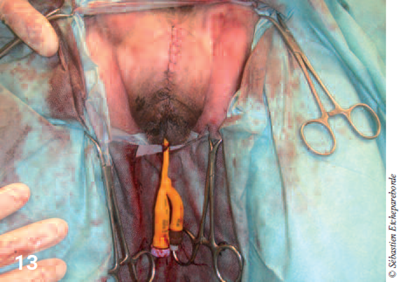

photo 13

Photo 13 – L’épisiotomie est refermée classiquement en 3 couches : surjet dans la muqueuse, dans le muscle puis la peau.

Après ressection, le vestibule est refermée par un surjet simple et des sutures résorbables puis l’épisiotomie est refermée en 3 plans (photos 11 à 14). La masse a été envoyée au laboratoire pour analyse histologique.